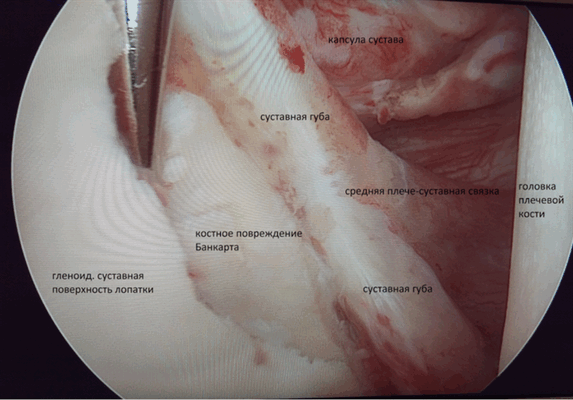

Вид изнутри на сустав.

- Нестабильное состояние плечевого сустава(повреждение Банкарта, вывих плеча, в том числе и первичный)

А) При переднем вывихе ПС вмешательство направлено на восстановление суставной губы (операция Банкарта). Метод нацелен на восстановление целостности суставной губы при помощи фиксации оторванной части на край суставного отростка лопатки.

В) В случае сочетания заднего повреждения Банкарта, сопровождающегося задним разрывом связки суставной впадины лопатки, артроскопия позволяет зафиксировать оторванную суставную губу к краю суставной впадины лопатки, заднюю часть капсулы плеча к задней части головки плеча. В качестве фиксатора используются биорассасывающие фиксаторы-якоря.

При повреждении плеча часто травмируется хрящевая губа. В итоге теряется стабильность сустава. Её потеря также связана с дефектом костного компонента суставной впадины лопатки (гленоида).

Положение тела пациента - «пляжное кресло». Для доступа делаются три небольших разреза. Определяется с помощью введенного в сустав артроскопа расположение поврежденной суставной губы. Она фиксируется. Проводится и фиксация суставной капсулы. Оценивается размер повреждения костной части гленоида. Устанавливаются якорные фиксаторы - от 3 до 5 штук, исходя из обширности повреждения.